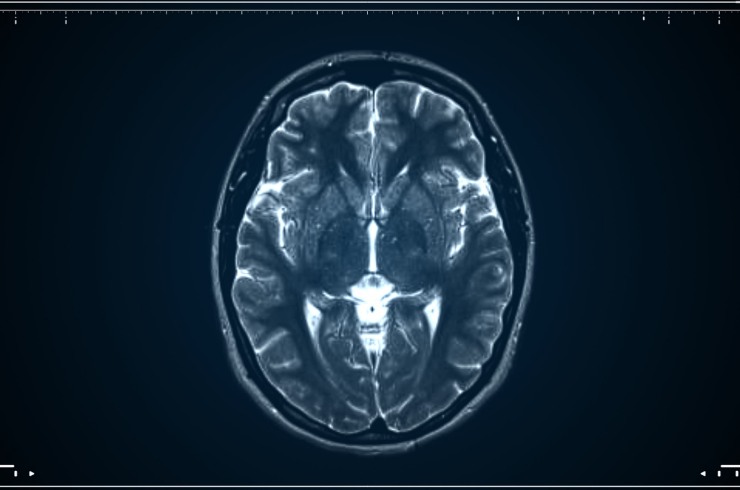

Medical care for brain and nervous system disorders focusing on accurate diagnosis, personalised treatment, and neurological health.

Surgical care for brain and spine conditions using precise techniques, modern technology, and expert specialists for improved outcomes.